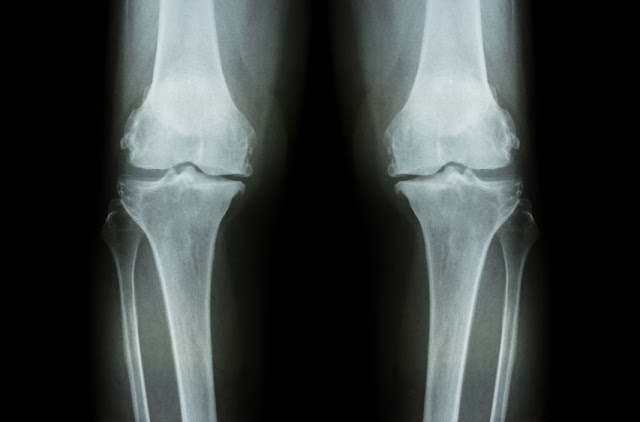

膝蓋是由股骨(大腿骨)、髕骨(膝蓋骨)、脛骨(小腿骨)三者組成的,骨頭跟骨頭之間又有一層軟骨作為緩衝、降低摩擦之用。膝蓋退化性關節炎的最大特色,就是這層軟骨的流失。(註1)

上面右圖是正常的膝關節,可以看到骨頭與骨頭之間有充足的空間,這層空間由軟骨所佔據。而左圖的膝關節內側的空間明顯變窄了,這意味著軟骨的厚度降低(註2)。

(註2:退化性關節炎並不是只有軟骨流失,周邊包括骨頭、韌帶、肌腱、肌肉、滑液膜等都會產生病理變化。)